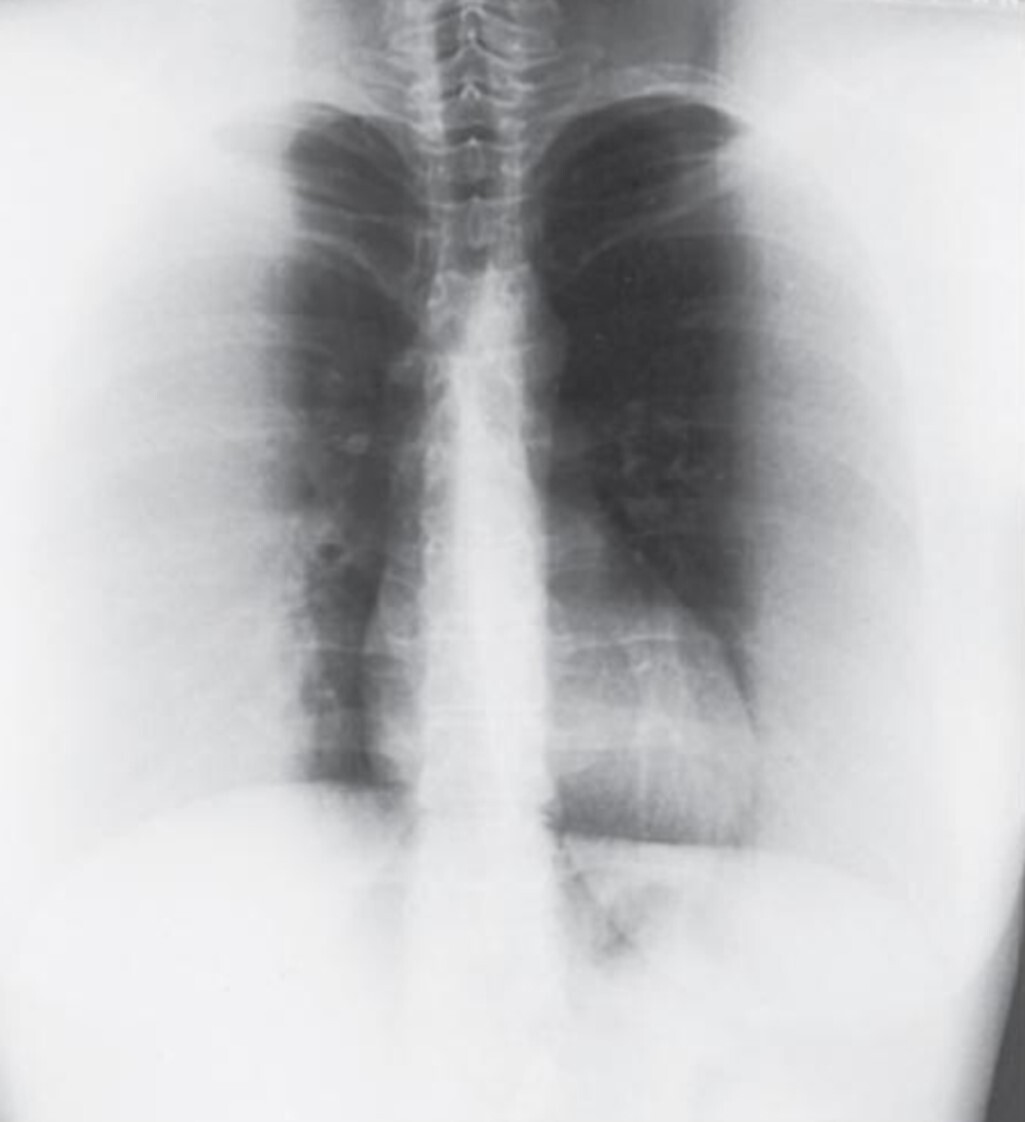

10

Q

What is the cause of the artifact seen in the

attached image?

A

Upside-down focused grid resulting in grid cut-off